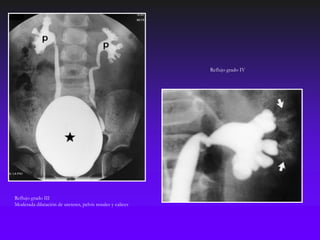

Reflujo grado IV

Reflujo grado III

Moderada dilatación de ureteres, pelvis renales y calices